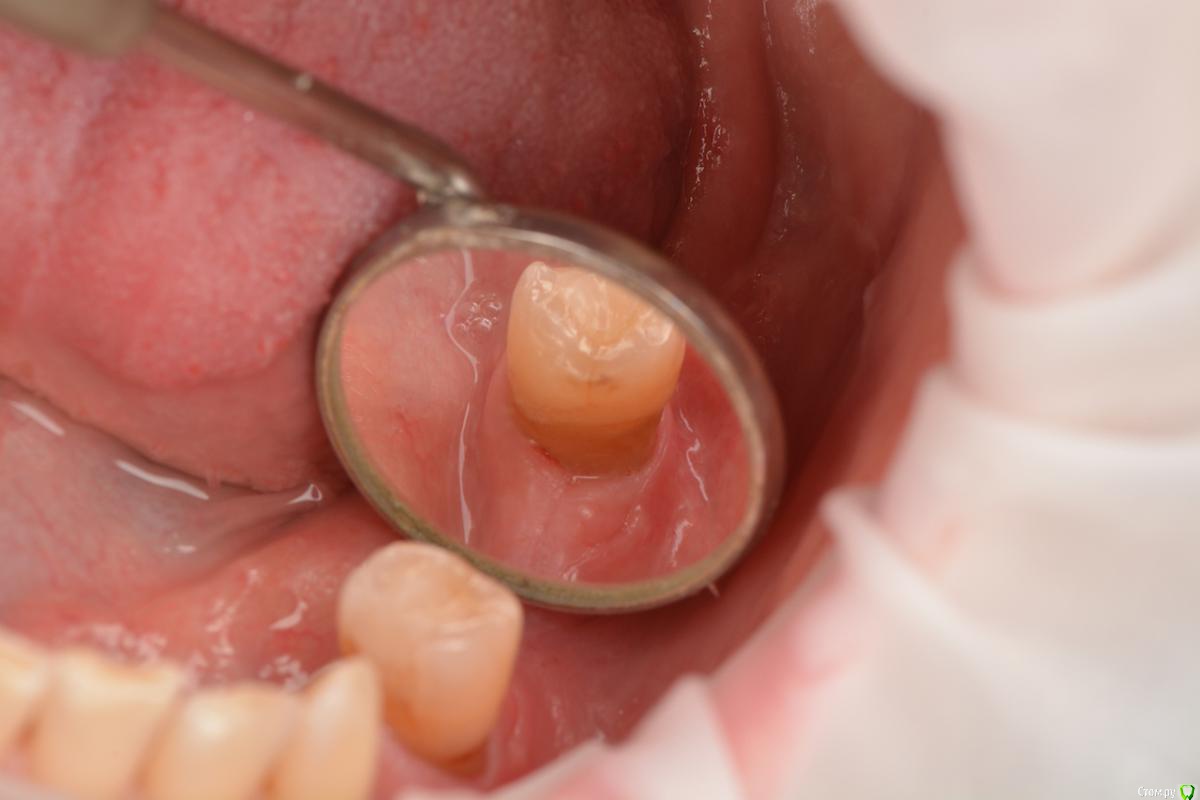

stommm Опубликовано 13 декабря, 2015 Поделиться Опубликовано 13 декабря, 2015 Всем доброго времени суток.Предыстория такая: в области 34 нкр с биооссом и биогайдом. В области 36 - биоосс+ауто+цитопласт, нагноение, долгие попытки вытянуть и в итоге ревизия и демонтаж мембраны. Отсроченно проведены установка имплантов и небольшое нкр в области 36. Десну по глупости сразу не добавил.Хочу перед расширением ЗПКД с помощью СДТ закрыть рецессию на 35. Вестибулярно думаю шансы неплохие, но дистально...? Планирую туннельный доступ через внутрибороздковый разрез. Как думаете. такого доступа хватит что бы завести и зафиксировать сст в области дистального сосочка? может сделать еще один небольшой разрез в области 36 и провести сст оттуда? Какие вообще шансы закрыть такую рецессию? Буду рад советам Ссылка на комментарий